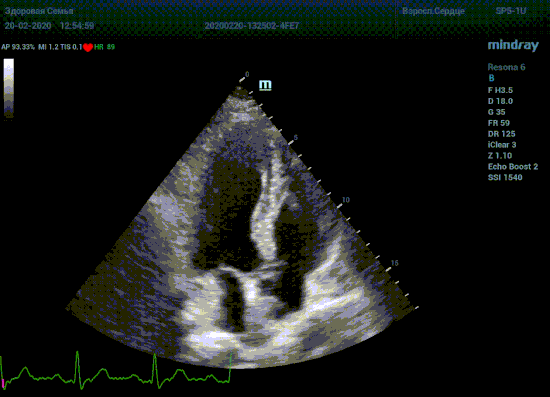

Терапия наиболее широкая область применения, однако взрослая кардиохирургия так же важное направление современной медицины. Оперировать аортальный стеноз, или же площадь клапана достаточная? Необходимо рассчитать площадь аортального клапана по уравнению непрерывности потока. Для этого нужно измерить на зуме выносящий тракт левого желудочка (LVOT) в середине систолы. Будем угадывать момент или возьмем середину Т зубца по ЭКГ? Доверимся интуиции при определении показаний к оперативному лечению или науке?

Детская кардиохирургия не исключение. Наиболее актуальная проблема — это дефекты межпредсердной и межжелудочковой перегородок, а также открытый артериальный проток. Не верная оценка гемодинамической значимости приведет к перегрузке правых отделов сердца и ряду осложнений, в случае если не прооперировать вовремя. Отправлять маленького ребенка под нож или подождать пока дефект перегородки зарастет сам? Ждем осложнений или ждать безопасно? На эти вопросы ответит Qp/Qs соотношение, рассчитанное методом эхокардиографии. Для этого необходимо рассчитать ударные объемы выносящих трактов желудочков, опять же на середине систолы – середине Т–зубца ЭКГ.